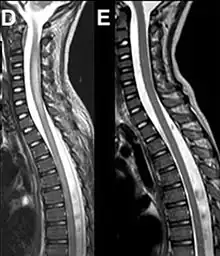

Magnetic resonance imaging of the spinal cord in a case of AFM showing cord swelling in (d) which has resolved three weeks later in (e).[2]